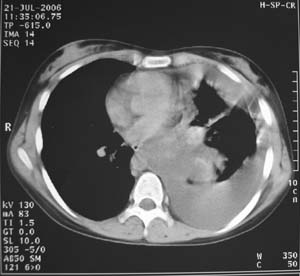

女性,17岁,一年前因股骨病变截肢,现胸憋。

左肺巨大肿块,内散在斑点状高密度骨化影,右肺见多发结节灶,双侧胸膜局限性增厚。有骨肉瘤病史,支持骨肉瘤手术后转移。